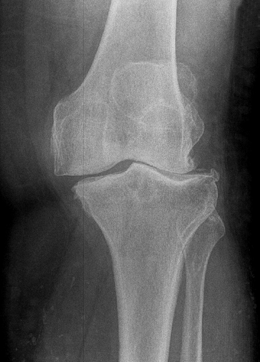

Ein typisches klinisches Zeichen einer Gonarthrose ist die schmerzhafte Bewegungseinschränkung des Kniegelenks. Die Schmerzen können in Ruhe und auch nachts sowie bei Bewegung des Kniegelenks, beim Gehen und Treppensteigen auftreten. Häufig tritt auch ein Reiben (Krepitation) oder Knarren bei Bewegung des Kniegelenks auf. Im Röntgenbild zeigen sich der Verlust des Gelenkknorpels, eine Entrundung der Gelenkflächen sowie Knochenanbauten (sogenannte Osteophyten) am Oberschenkel- und Unterschenkelknochen. Bei einigen Patienten tritt eine zunehmende Fehlstellung der Beinachse (X-Bein-Stellung oder O-Bein-Stellung) auf.